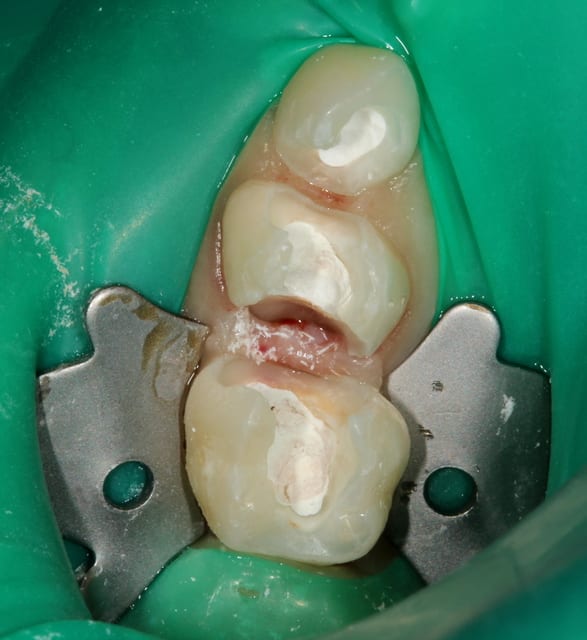

=> Crampons dentelés 12A ou 13A.

=> Technique "Split Dam" : deux perforations fusionnées dans ta feuille, bague sur la 5, tu étires jusqu'à la pointe canine.

Img 1613 vjgwcd - Eugenol

Img 1919 afymqb - Eugenol